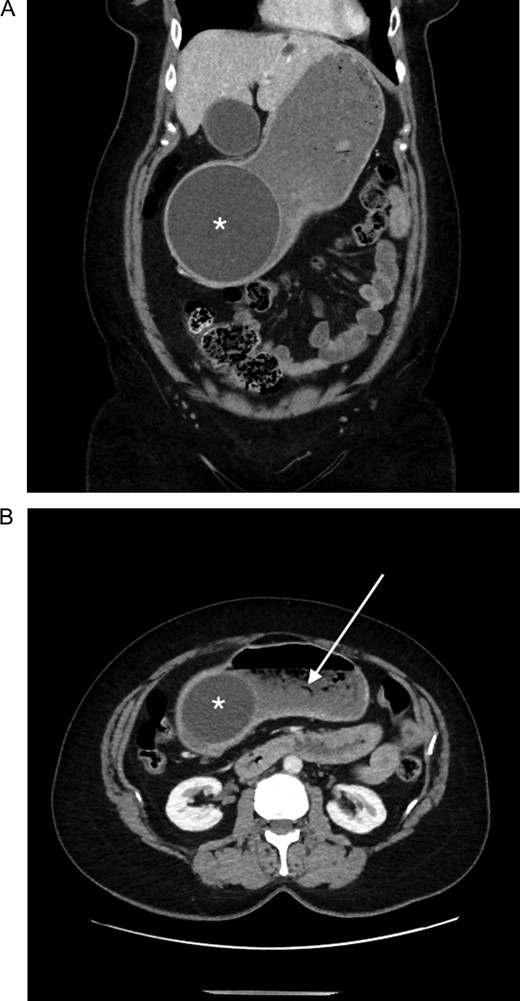

In initial erect chest X-ray was unremarkable for any evidence of pneumoperitoneum. A subsequent contrast abdominal computed tomography (CT) study demonstrated a large intragastric balloon within the gastric antrum, containing fluid and a small amount of gas, measuring 115 mm × 96 mm × 116 mm diameter (Fig. 1). Above this, the gastric fundus and body were moderately distended and contained a fairly large amount of ingested fluid and gas (Fig. 1).

Abdominal computed tomography showing (A) an intragastric balloon within the gastric antrum (asterisk), with (B) a moderately distended fluid and gas filled gastric fundus and body (arrow).